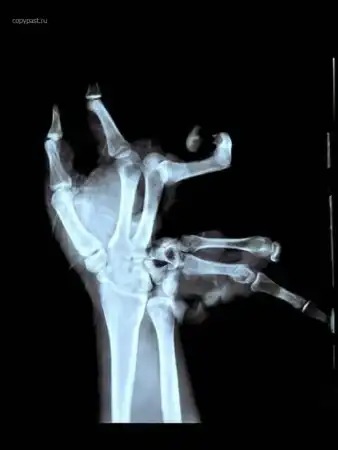

Парень держал в руке самодельную взрывчатку, та взорвалась